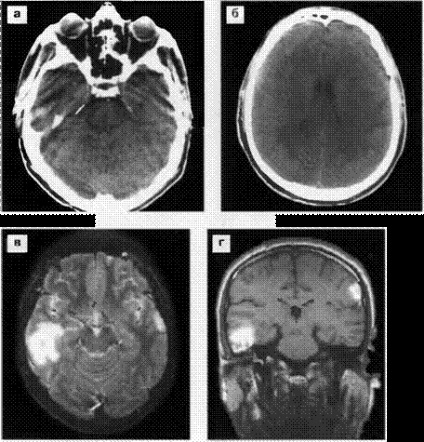

Ábra. 19. zúzódás gócok a jobb parietotemporalis és elhagyta az alagsorban (a típus protivoudara) területeken. CT (a, b) 8 órás traumás agysérülés után: kis zsebek sûrûsödések jobb temporo-bazális és a bal parietális területek a jobb oldalsó agykamra elhagyta, az elmozdulás a kamrai rendszer nem. MRI T2 (a) és T1 (g) módok: magas jel gócok a jobb temporo-bazális, a bal oldali temporális és parietális területeken.

Ábra. 22. Egy kis intracerebralis hematóma a bal frontális régióban. MRI dinamika: a, b - az első nappal a sérülés után: T2 mód haematoma van egy alacsony jel T1 üzemmód - jelet haematoma izointensivny, perifocal ödéma T2 - giperintensiven MRI 7 nappal a trauma után (c, d) - haematoma ez hyperintensive jel mindkét üzemmódban miatt methemoglobinná.